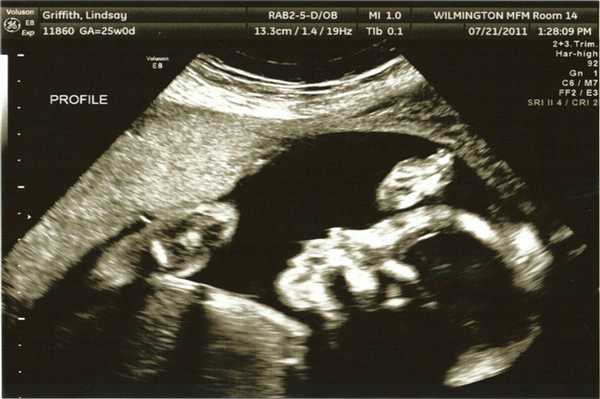

Фото УЗИ ребенка на разных сроках беременности

Если беременность желанная, будущие родители внимательно относятся к пренатальной диагностике плода. Чтобы убедится, что ребенок развивается нормально, в течение 9 месяцев гинеколог несколько раз направляет женщину на ультразвуковое исследование. Фото УЗИ может многое рассказать врачу и будущим родителям о малыше. Кроме того, снимок станет трогательным напоминанием для семейного архива.

Чтобы сделать фото УЗИ малыша на разных сроках, беременной женщине необходимо записаться на ультразвуковой скрининг в медицинском центре «Диана».

Фото УЗИ ребенка на 23-24 неделе беременности

В этот период малыш очень активный. Его мышцы и костные структуры позволяют совершать координированные интенсивные движения, а относительно небольшие размеры обеспечивают свободное пространство. Конечности и пальцы удлиняются. Ребенок совершает дыхательные движения, глотая околоплодную жидкость. Его кожа и подкожная жировая прослойка утолщаются. УЗИ на этом сроке назначают редко.